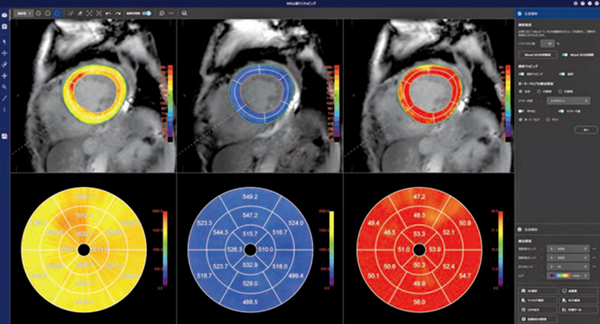

■MR心筋T1マッピング

T1マッピングは,浮腫,壊死,線維化などの心筋ダメージの評価が可能で,早期病変の検出や重症度・予後の評価,治療効果判定などに有用とされており,日本循環器学会の「2020年版 心アミロイドーシス診療ガイドライン」や「2023年改訂版 心筋炎の診断・治療に関するガイドライン」では,推奨クラスⅠと強く推奨されている。心筋症の診断においては,造影前(native)と造影後(enhanced)のT1値を用いた細胞外容積分画(extracellular volume fraction:ECV)を組み合わせることで鑑別診断が可能となる。遅延造影で特定の難しい心アミロイドーシスや心筋炎などのびまん性の病変に対する診断への活用が期待されている。

REVORASの「MR心筋T1マッピング」では,データを開くと非剛体位置合わせやinversion time(TI)間の位置ズレ,造影前後の位置ズレの補正が自動で実行される。左室解析ステージでは,左室内腔と外壁の自動抽出を基にセグメントごとのT1値の評価を確認でき,native/enhanced/ECVのセグメントごとの解析結果がポーラーマップ上に表示され,同時に観察することができる。全体解析ステージでは,画像全体に対するT1値の算出や,関心領域の設定による任意の領域のT1値評価を簡便に行うことが可能である。解析ワークフローの改善によりデータオープンから解析結果表示までの時間短縮が図られ,新たなバージョンからはレイアウトも一新し,より効率的に解析業務をサポートする(図1)。

図1 MR心筋T1マッピング